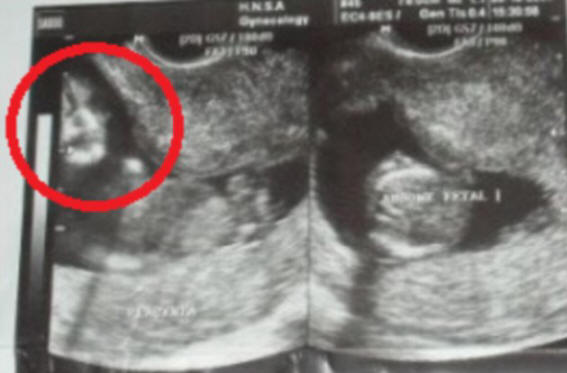

Zakonca Marcelo in Famela de Souza (Marcelo in Phamela de Souza) so bili šokirani, ko so na ultrazvoku videli svojega nerojenega otroka podoba, podobna obrazu pokojne matere Marcelo.

Na eni od slik se je naenkrat od nekod pojavil čuden “obraz” iz maternice

Postopek so izvedli pri 10 tednih nosečnosti in bodočega očeta takoj na zaslonu opazil čudno sliko, a se je bal povedati o tem svoji ženi. Vendar je sama kmalu videla obraz na fotografiji in pokazala možu. Po Marcelovem mnenju je bilo zelo podobno kot obraz njegove matere, ki je umrla le 4 mesece pred tem.